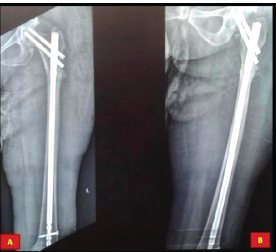

Fracture Occurrence following Prophylactic Nailing in a Case of Bisphosphonate-induced Atypical Femoral Fracture – A Rare Case Report

Kumardev Arvind Rajamanya , Tushar Nayak , Rahul Shah

………………………………p.116-120